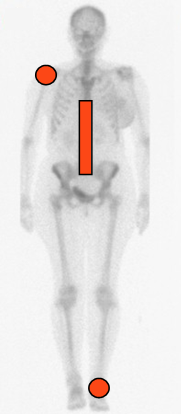

Fig 40. Distribución de la artropatía neuropática.

Compromiso aislado del hombro, tobillo, pie o columna, asociado a una patología desencadenante.